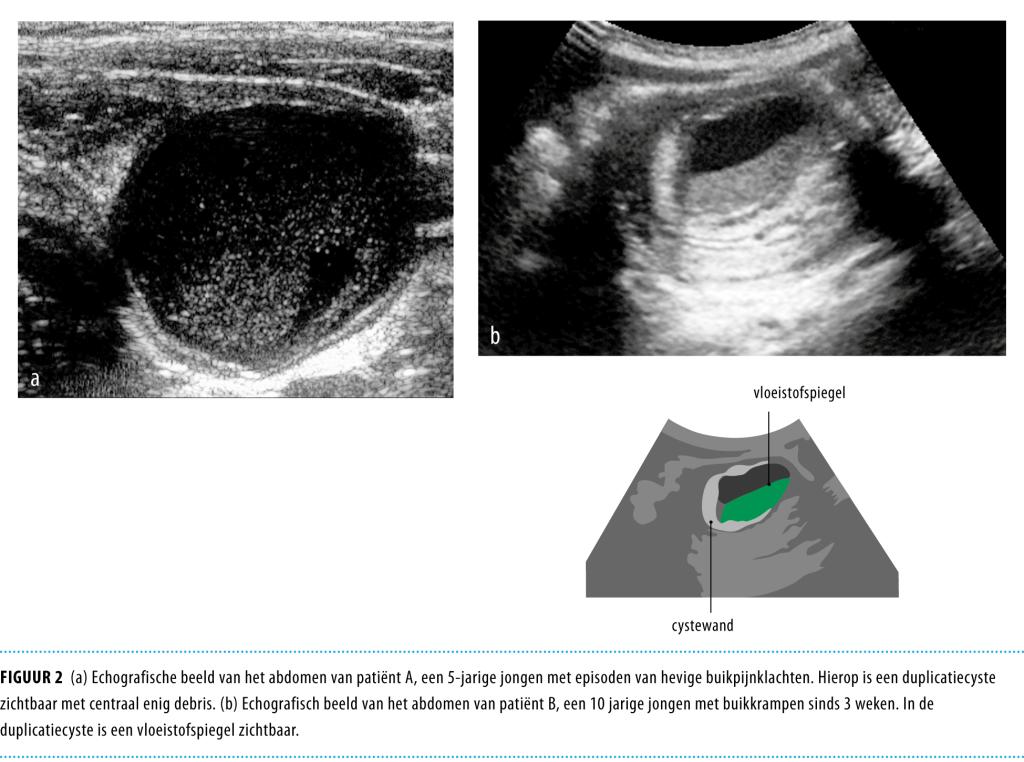

Een 5-jarige jongen werd gezien voor een second opinion vanwege episoden van hevige abdominale pijnklachten en een wisselend bolle buik. Echografisch onderzoek liet een afwijking zien verdacht voor een duplicatiecyste in het terminale ileum. Er werd een laparoscopisch geassisteerde resectie uitgevoerd, waarna de diagnose ‘duplicatiecyste’ bevestigd werd door histologisch onderzoek. Een aantal maanden later werd een 10-jarige jongen gezien met buikpijnklachten, diarree en braken. De abdominale echografie liet een invaginatie zien tot halverwege het colon transversum, alwaar een grote cyste-achtige structuur met vloeistofspiegel aanwezig was. De invaginatie werd laparoscopsisch opgeheven en er volgde een resectie van een duplicatiecyste van het ileum. Een duplicatiecyste van de darm is een zeldzame diagnose (prevalentie 1: 4500), maar het is belangrijk van het bestaan af te weten. Laparoscopie is een elegante manier voor resectie van de duplicatiecyste bij kinderen.